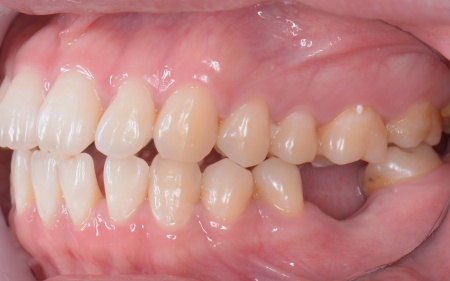

20代女性 歯の根が割れた歯を抜歯したあと矯正治療と骨再生を併用したインプラント治療で補った症例

また、上下の歯を噛み合わせた際に前歯が噛み合わず隙間ができる開咬(かいこう)と呼ばれる噛み合わせも見られました。

開咬は奥歯に負担が集中しやすく、その影響で今回のように歯の根が割れてしまった可能性が高いと考えられます。

まず、右上と左下の奥歯を抜歯しました。

その後、全体の噛み合わせを改善するため、矯正治療を開始しています。